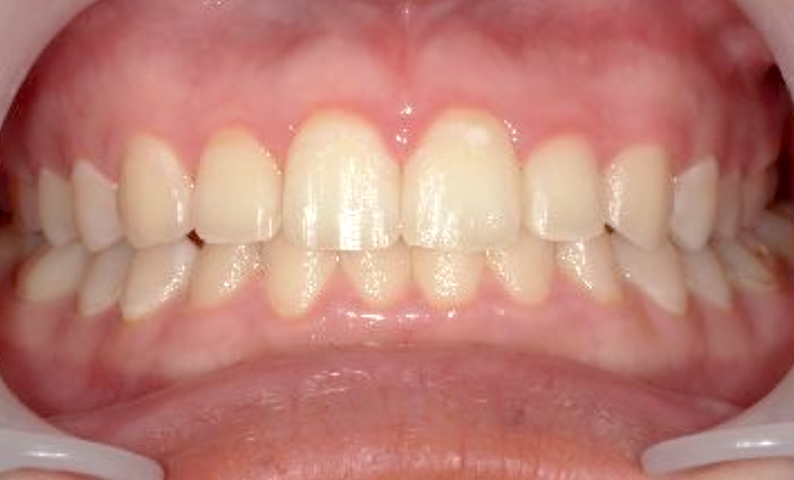

症例:上下顎の部分矯正

症例_002 前歯「すきっ歯」症例

治療期間:8ヶ月金額:48万円+税20代女性すきっ歯